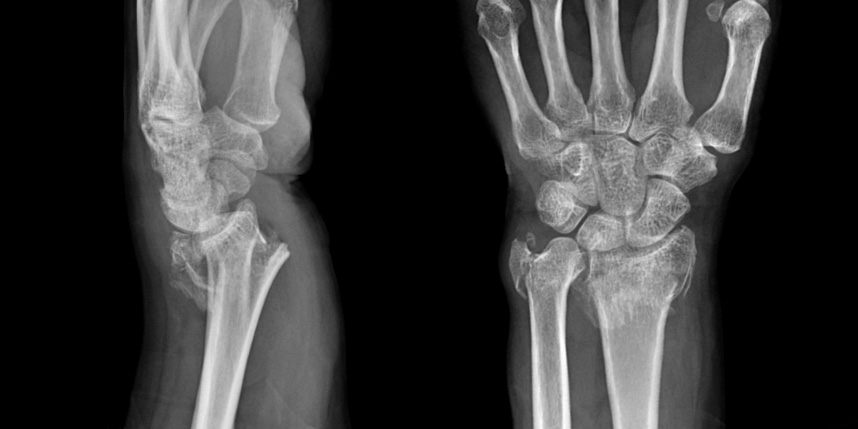

손목 골절